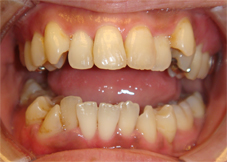

笑った時の八重歯を気にして来院された患者さまです。

写:矯正治療前、右:治療後

上下とも八重歯の状態が治療後は改善しています。歯並びがきれいに並んで、その後ホワイトニングも行いました。

前歯の歯並びのでこぼこも解消しました。

上の前歯が前に突出していた状態も改善して前歯が引っこんでいます。

前歯の歯並びが改善すると笑った時の雰囲気もかなり変わりますよね。この後すぐに結婚式が控えておりましたが、ホワイトニングも行って挙式に臨んでいただきました。